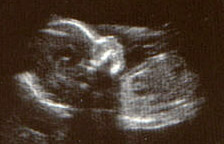

Most of you will be familiar with the idea that unborn babies can be photographed - if rather unclearly - by using ultrasound. This is safe compared to X-rays, which may damage the child.

ultrasound scan of baby in womb

Apart from giving parents the first photograph for the album, it allows doctors to check for certain birth defects, checking its size - and even if there is more than one!